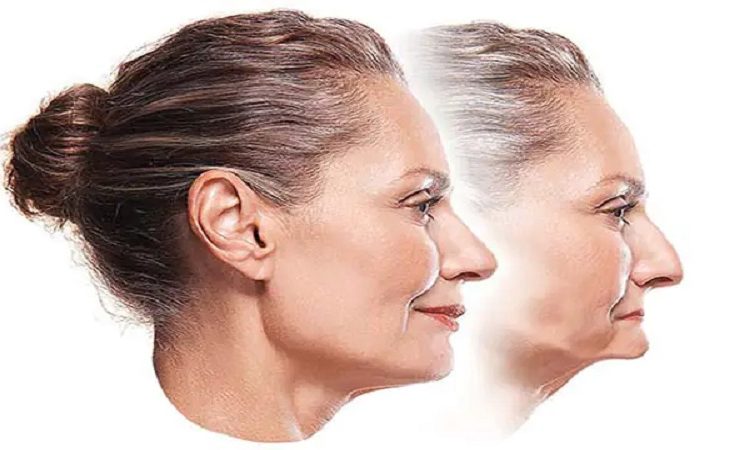

عوارض تحلیل و از دست رفتن استخوان فک چیست؟ از دست دادن استخوان فک میتواند: عوارض جدی برای سلامت دهان و دندانها و همچنین برای ظاهر و کیفیت زندگی فرد ایجاد کند. برخی از اصلیترین عوارض از دست دادن استخوان فک عبارتند از: ضعف و ناهنجاری ساختار فکها با تجزیه استخوان فک، فکها کمتر از

از دست دادن استخوان فک به چه معناست؟ تجزیه استخوان فک(کاهش تراکم استخوان فک) از دست دادن استخوان فک به معنای کم شدن یا تخریب استخوانهایی است که در فکهای بالا و پایین وجود دارد. این مسئله اغلب به عنوان “تجزیه استخوان فک” یا “کاهش تراکم استخوان فک” نیز شناخته میشود. وقتی که یک شخص